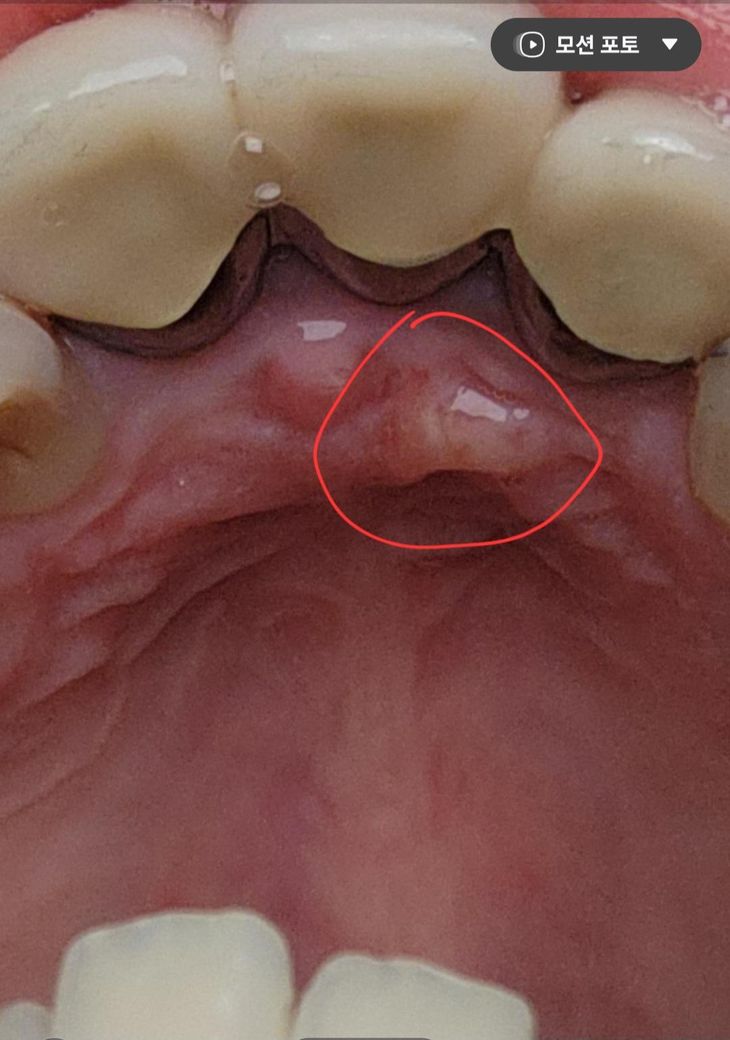

잇몸 입천장쪽에 생긴 이것은 무엇일까요~?

잇몸 입천장쪽에 생긴 이런게 생겼습니다.

생긴지는 한달정도 된것 같은데 혹시 무엇일까요~?

• 1번 째 사진

입천장이 자극을 받아서 생긴 염증일수도 잇지만 치아때문에 생긴 염증일수도 잇으니 치과에 가셔서 일단 치과에 가셔서 엑스레이를 찍어보시는게 좋을것같습니다

사진상 농양이 생긴 것으로 보입니다. 씌운 치아가 신경치료가 되어 있다면 재신경치료, 신경치료가 안되어 있다면 신경치료가 필요할 수 있겠습니다